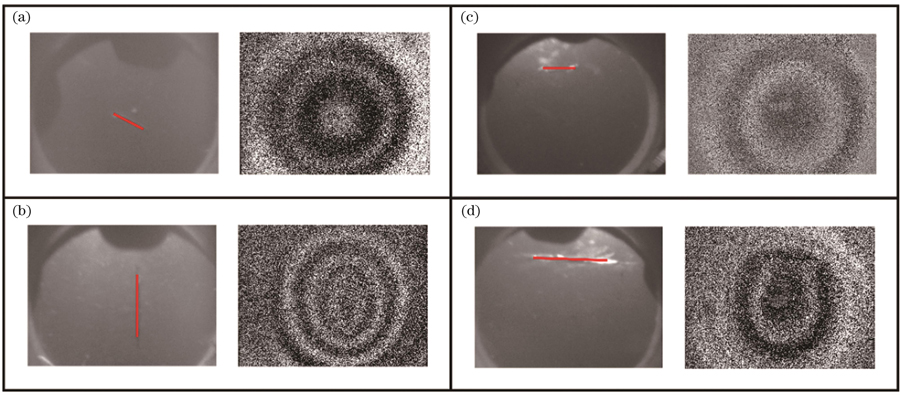

图 11. 穿孔薄膜的一阶振动模态图。(a)中心穿孔3 mm薄膜;(b)中心穿孔5 mm薄膜;(c)偏心穿孔3 mm薄膜;(d)偏心穿孔5 mm薄膜

Fig. 11. First-order vibrational mode diagrams of perforated films. (a) Film with a 3 mm diameter perforation in the center; (b) film with a 5 mm diameter perforation in the center; (c) film with an eccentric 3 mm diameter perforation; (d) film with an eccentric 5 mm diameter perforation

针对上述的薄膜划伤仿真分析,同样进行了相应的实验验证,得到的中心划痕样本的一阶振动模态图如

图 12. 划伤薄膜的一阶振动模态图。(a)中心3 mm划伤薄膜;(b)中心6 mm划伤薄膜;(c)偏心3 mm划伤薄膜;(d)偏心6 mm划伤薄膜

Fig. 12. First-order vibrational mode diagrams of scratched films. (a) Film with a 3 mm scratch in the center; (b) film with a 6 mm scratch in the center; (c) film with an eccentric 3 mm scratch; (d) film with an eccentric 6 mm scratch